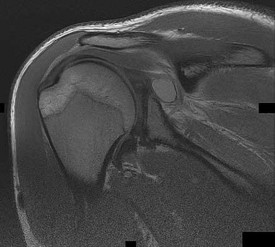

Question 33:

A 21-year-old collegiate rugby player presents with recurrent anterior shoulder instability. He has had 5 dislocations over the past year. A 3D reconstructed CT scan of the shoulder reveals an inverted-pear glenoid with an estimated 28% anterior inferior bone loss. Which of the following surgical interventions provides the most reliable biomechanical stability and lowest recurrence rate for this specific patient?

Correct Answer: Latarjet procedure

Explanation:

Anterior glenoid bone loss exceeding 20-25% (often described visually as an 'inverted pear' glenoid) is a critical threshold in anterior shoulder instability. Soft tissue procedures alone, such as arthroscopic or open Bankart repairs, have unacceptably high failure rates in this setting. The Latarjet procedure (transfer of the coracoid process with the attached conjoint tendon to the anterior glenoid) reconstructs the bony arc and provides a dynamic sling effect, making it the standard of care for critical glenoid bone loss.